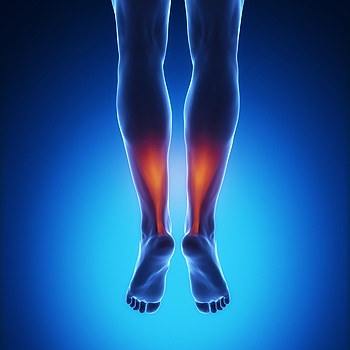

Symptoms of Poor Circulation in the Feet

One of the first ways to tell if poor circulation exists in the feet is by the numbness and tingling that is often experienced. More severe examples may be a cold feeling that develops in the feet in addition to possible cramping. Poor circulation may be a symptom of vascular disease which often occurs with blocked arteries. When this occurs, the blood is not carrying adequate amounts of oxygen to and away from the heart, and this is often noticed in the feet. The development of sores on the feet may be a sign that poor circulation exists, and may have difficulty in healing properly. You may also notice a slower growth pattern in your toenails If you feel you may have poor circulation in your feet, speaking with a podiatrist is recommended.

One of the first ways to tell if poor circulation exists in the feet is by the numbness and tingling that is often experienced. More severe examples may be a cold feeling that develops in the feet in addition to possible cramping. Poor circulation may be a symptom of vascular disease which often occurs with blocked arteries. When this occurs, the blood is not carrying adequate amounts of oxygen to and away from the heart, and this is often noticed in the feet. The development of sores on the feet may be a sign that poor circulation exists, and may have difficulty in healing properly. You may also notice a slower growth pattern in your toenails If you feel you may have poor circulation in your feet, speaking with a podiatrist is recommended.

While poor circulation itself isn’t a condition; it is a symptom of another underlying health condition you may have. If you have any concerns with poor circulation in your feet contact one of our podiatrists of APEX Foot & Ankle Center. Our doctors will treat your foot and ankle needs.

Poor Circulation in the Feet

Peripheral artery disease (PAD) can potentially lead to poor circulation in the lower extremities. PAD is a condition that causes the blood vessels and arteries to narrow. In a linked condition called atherosclerosis, the arteries stiffen up due to a buildup of plaque in the arteries and blood vessels. These two conditions can cause a decrease in the amount of blood that flows to your extremities, therefore resulting in pain.

Symptoms

Some of the most common symptoms of poor circulation are:

- Numbness

- Tingling

- Throbbing or stinging pain in limbs

- Pain

- Muscle Cramps

Treatment for poor circulation often depends on the underlying condition that causes it. Methods for treatment may include insulin for diabetes, special exercise programs, surgery for varicose veins, or compression socks for swollen legs.

As always, see a podiatrist as he or she will assist in finding a regimen that suits you. A podiatrist can also prescribe you any needed medication.

If you have any questions, please feel free to contact our offices located in Fort Myers, Cypress Cove, Shellpoint, Naples, and Carlisle, FL . We offer the newest diagnostic and treatment technologies for all your foot care needs.

Causes, Symptoms, and Treatment of Poor Blood Circulation in the Feet

Poor blood circulation in the feet and legs is often caused by peripheral artery disease (PAD), which is usually the result of a buildup of plaque in the arteries. Plaque buildup, or atherosclerosis, can be the result of excess calcium and cholesterol in the bloodstream. This restricts how much blood can flow through arteries. Reduced blood flow to a certain area of the body severely limits the amount of oxygen and nutrients that part of the body receives. This leads to degeneration in the muscles and other tissues. Sometimes, poor blood circulation in the feet and legs can be caused by other conditions, such as the damaging or inflammation of blood vessels, known as vasculitis.

The lack of oxygen and nutrients caused by poor blood circulation can restrict muscle growth and development, as well as cause muscle pain and cramps, weakness, and stiffness. Other common symptoms include numbness in the legs and feet, skin discoloration in the affected limbs, slower nail and hair growth, and erectile dysfunction in men. In more severe cases of PAD, pain can be present even when a person isn't exercising, and may range from mildly uncomfortable to completely debilitating.

Poor blood circulation in the feet and legs is more common in those who are overweight or obese, have diabetes, high blood pressure, high cholesterol, who smoke, or who have a family history of PAD or related conditions such as a heart attack, stroke, etc. Diabetes and smoking place a person at greatest risk for developing poor blood circulation, although advanced age, over 50, can also increase risk.

If you are experiencing poor blood circulation in the feet and legs caused by PAD, it is important to make changes to your lifestyle in order to reduce your risk of experiencing a heart attack or stroke caused by this condition. If you smoke, quit completely. This will increase the amount of oxygen in your bloodstream. Exercising and reducing the saturated fats in your diet. Saturated fats come from fatty meats, fried foods, whole milk, etc., can make a difference in improving blood circulation in feet. It is also important to avoid developing influenza and to carefully control your blood sugar if you have diabetes.

Your doctor may recommend combining lifestyle changes with a prescription medication regimen to improve blood circulation. The most commonly-used medications for PAD are called statins and work by blocking the amount of enzymes in your body that produce cholesterol. They are known by the brand names Zocor, Lipitor, Crestor, and others.